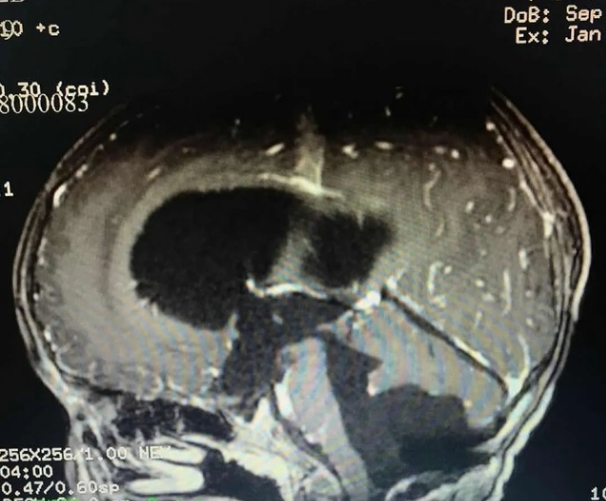

小乐手术后CT影像

据悉,该类肿瘤术后5年和10年的生存率很高。当肿瘤侵及脑干、脑神经或血管,可能导致肿瘤切除受限,因肿瘤复发亦会缓慢生长。如果在这期间进行放射治疗,并发症发生率较高。陈陆馗建议,此类患者术后不行放射治疗,只需定期随访复查CT或MRI,必要时应再次手术根治。